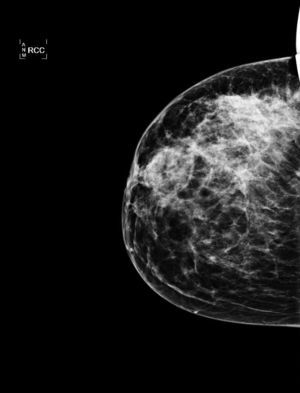

Caso clínicoMujer de 38 años, que acude a urgencias de nuestro hospital el 14 de octubre del 2010 por presentar un proceso inflamatorio, supurativo y doloroso en el cuadrante supero-externo de la mama derecha. Entre de sus antecedentes familiares, encontramos hermana con cáncer de mama. Antecedentes personales ginecoobstétricos: gestaciones 3; abortos uno; partos 2, con última gestación hace 5 años; anticoncepción con preservativo; el resto, sin interés. En la exploración, se aprecia todo el cuadrante supero-externo de la mama derecha eritematoso, caliente y con un punto de drenaje a piel, por lo que se piensa en una mastitis aguda y se inicia tratamiento con cloxacilina 500mg cada 6 h durante 7 días, estreptoquinasa 40mg cada 12 h y analgesia. Cuatro días después, se evidencia un empeoramiento del cuadro, objetivándose una masa de 6cm de diámetro y pezón derecho umbilicado y adenopatías axilares de tamaño patológico. Se cambia el tratamiento antibiótico por amoxicilina-clavulánico 875/125 cada 8 h durante una semana y se solicitan mamografía y ecografía mamaria (figs. 1 y 2). Por las características del proceso, se piensa en un cuadro inflamatorio/infeccioso, con un área de probable caseificación o en un carcinoma inflamatorio.

Mamografía: se observa un aumento difuso de la radiodensidad, con claro incremento de la trabeculación, preferentemente a nivel de los cuadrantes externos, más focalizada en el cuadrante supero-externo. También afecta al plano cutáneo, preferentemente a nivel del complejo aréola-pezón, el cual engrosa y retrae.

La mamografía, la ecografía y la RMN son usadas principalmente para excluir malignidad más que para diagnosticar la mastitis granulomatosa, ya que las imágenes obtenidas no son específicas. La mamografía puede darnos signos indistinguibles de un carcinoma. La ecografía nos puede mostrar una imagen hipoecogénica e irregular con sombra posterior o con la presencia de zonas tubulares. La RMN puede ser útil en la evaluación de la extensión de la lesión y en la evolución. Puede mostrar hipodensidad central, hiperintensidad periférica, lesión heterogénea o una lesión circunscrita con captación heterogénea del contraste2-9.